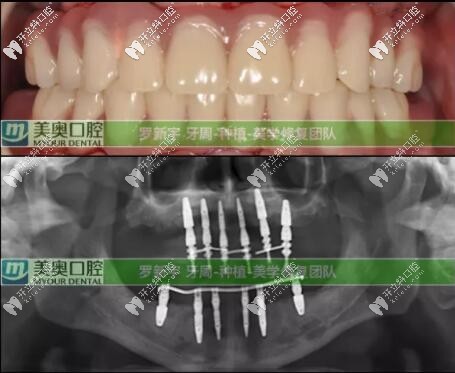

接著就是種植牙修復(fù)計劃:根據(jù)臨床上的口腔數(shù)據(jù),根據(jù)顧客的實際情況選擇了Straumann? Pro Arch無牙頜種植修復(fù)解決方案,拔除全部松動的余留牙,雖然犧牲可能有點大,但換來的是全口好牙還有自信。

全口即刻負重種植就是:在當(dāng)天種植并完成臨時修復(fù),PS:臨時修復(fù)是指臨時牙冠。為患者帶上臨時牙,可實現(xiàn)當(dāng)天吃蘋果的愿望。即刻修復(fù)就是這么快。后期又進行了為期六個月的復(fù)診和跟蹤治療;

六個月后口腔檢查評價:種植體全部存留、臨時修復(fù)體存留、終末修復(fù)體(長久性的牙冠)存留;可以說這次種植修復(fù)是很成功的。